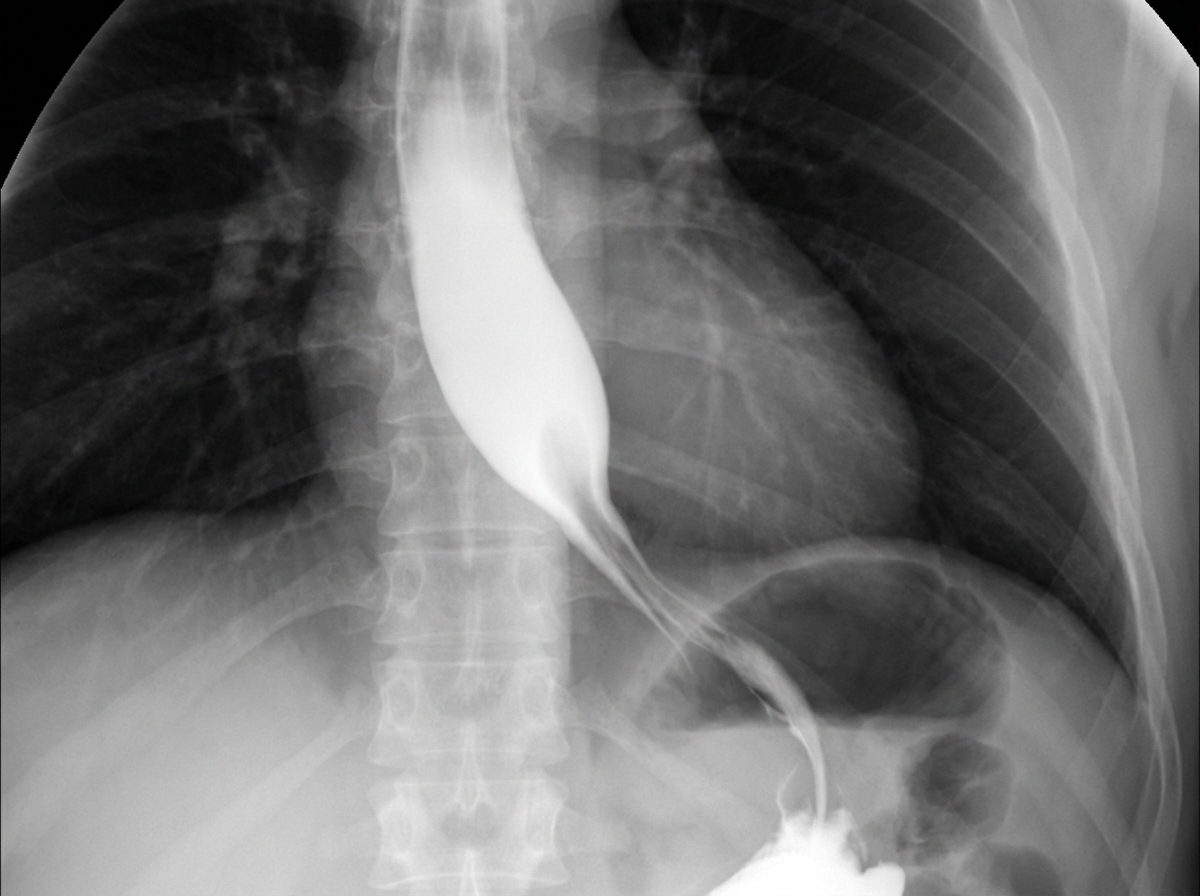

A 56-year-old woman comes to the physician because of a 6-month history of difficulty swallowing food. Initially, only solid food was problematic, but liquids have also become more difficult to swallow over the last 2 months. She also reports occasional regurgitation of food when she lies down. The patient is an avid birdwatcher and returned from a 3-week trip to the Amazon rainforest 3 months ago. She has had a 3.5-kg (7.7-lb) weight loss over the past 6 months. She has not had abdominal pain, blood in her stools, or fever. She underwent an abdominal hysterectomy for fibroid uterus 6 years ago. She has smoked a pack of cigarettes daily for 25 years. Current medications include metformin and sitagliptin. The examination shows no abnormalities. Her hemoglobin concentration is 12.2 g/dL. A barium esophagram is shown. Esophageal manometry monitoring shows the lower esophageal sphincter fails to relax during swallowing. Which of the following is the next best step in management?